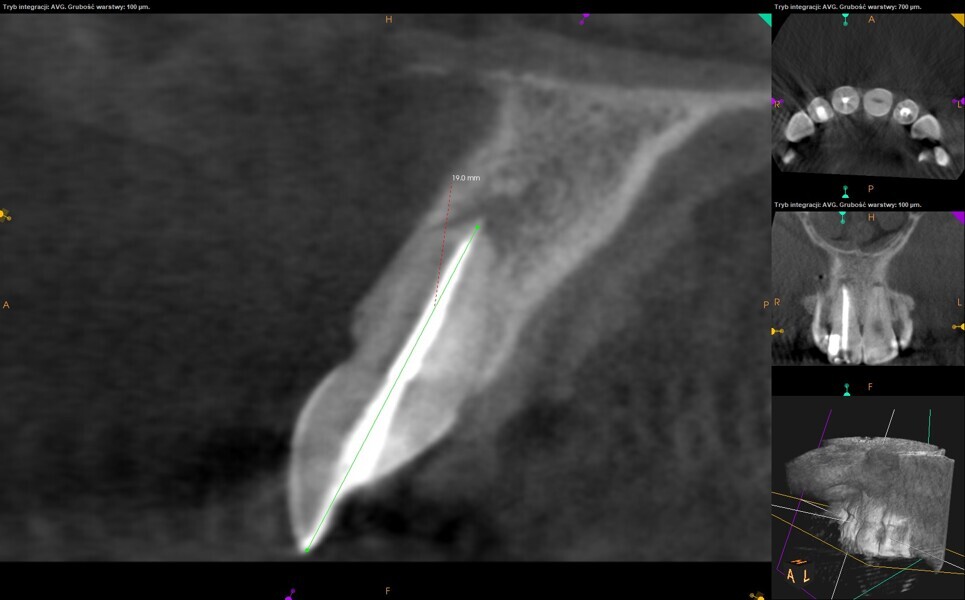

During the consultation, the CBCT scan was performed with the 9000 C 3D with a voxel size of 0.1 mm (Carestream). The CBCT scan revealed a highly calcified pulp chamber and an almost invisible trace of the root canal (Fig. 2). The patient was informed about the new, beneficial technology which can help to preserve additional tooth structure during treatment.

Figs. 2a & b: CBCT scan, sagittal (a) and coronal planes (b). Visible pulp canal obliteration and periapical lesion.

Fig. 12: CBCT check, sagittal plane. Measurement of the root thickness conrmed the size of the preparation. Healing of the periapical tissue was observed.

Fig. 13: CBCT check, sagittal plane. The long axis of the root and the axis of the access cavity and root canal preparation were visible.